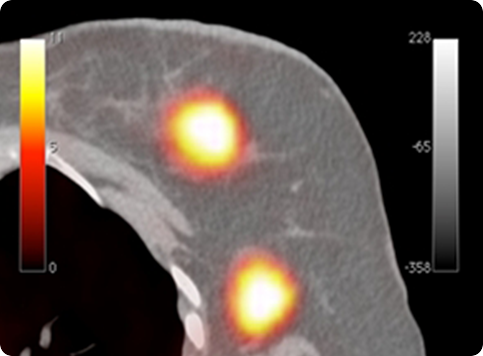

Clear-PEM and the corresponding whole-body PET/CT exams. Tumors not seen on PET/CT are identifiable using PEM (data collected at Hospital Nord - Marseille).

Due to its very good spatial resolution and accessibility of

the Field-of-View,

the Clear-PEM system can also

be used for small animal imaging.

Clear-PEM and the corresponding whole-body PET/CT exams. Tumors not seen on PET/CT are identifiable using PEM (data collected at ICNAS – Coimbra)